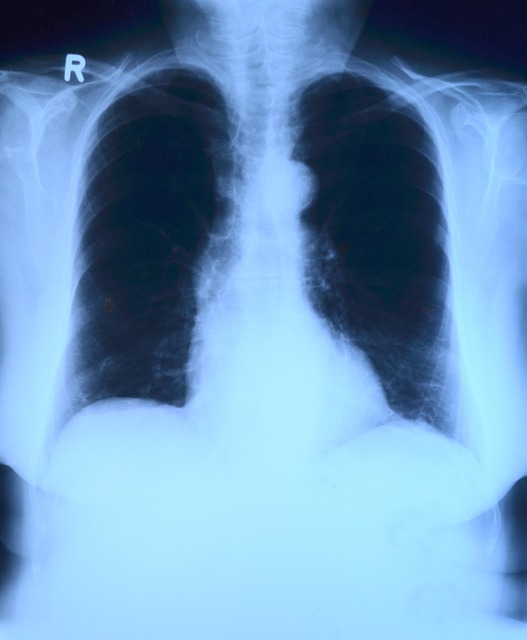

폐렴은 폐에 염증이 생기는 질환으로 세균, 바이러스, 곰팡이 등에 의해 발생합니다. 폐의 폐포(공기주머니)에 염증이 생겨 산소 교환이 어려워지고, 심한 경우 호흡부전으로 발전할 수 있습니다. 이러한 폐렴의 주요 원인으로는 세균 감염(폐렴구균, 황색포도상구균, 마이코플라스마 등), 바이러스 감염(인플루엔자(독감), 코로나19, RSV 등), 곰팡이 감염(면역력이 약한 사람에게 주로 발생함), 흡입성 폐렴(음식물, 위산 등이 폐로 들어가 염증 유발)이 있습니다. 이러한 감염의 주된 경로는 감기, 독감이 악화되면서 폐로 감염이 확산되는 경우, 바이러스나 세균의 공기 중으로 전파되는 경우, 면역력이 약한 사람에게 기회감염이 발생하는 경우 등이 있습니다. 이러한 폐렴에 걸리기 쉬운 고위험군은 면역력이 저하된 65세 이상의 노인, 폐 발달이 완성되지 않은 5세 이하의 영유아, 만성 질환 환자(당뇨병, 심장병, COPD 등), 기타 면역저하자(암 치료 중인 환자, 장기 이식 환자, 스테로이드 복용자 등)입니다.

폐렴이 심해지면 폐포에 염증이 가득 차면서 산소 공급이 어려워지고 심각한 합병증이 발생할 수 있습니다. 폐렴의 진행 과정을 단계에 따라 나누면 다음 표와 같은 특징을 가집니다.

이러한 증상으로 폐렴이 악화될 경우 생길 수 있는 합병증 또한 여러 가지가 있습니다. 첫 번째로 급성 호흡부전 (ARDS, Acute Respiratory Distress Syndrome)으로 폐에 심한 염증이 생겨 산소 공급이 어려워지는 상태를 말하여 인공호흡기를 이용한 치료를 하게 될 가능성이 있습니다. 두 번째는 패혈증 (Sepsis)으로 폐렴이 혈류로 퍼지면서 전신 감염 유발하여 신장 및 간 기능 장애, 쇼크 상태 위험성이 있습니다. 세 번째는 심장 합병증으로 폐렴으로 인한 심장의 부담이 증가하여 심부전, 심근염 유발 가능합니다. 마지막으로 만성 폐질환 유발을 유발할 수 있습니다. 반복적인 폐렴이 폐 조직을 손상시켜 천식과 COPD의 위험성 증가시킬 수 있습니다.